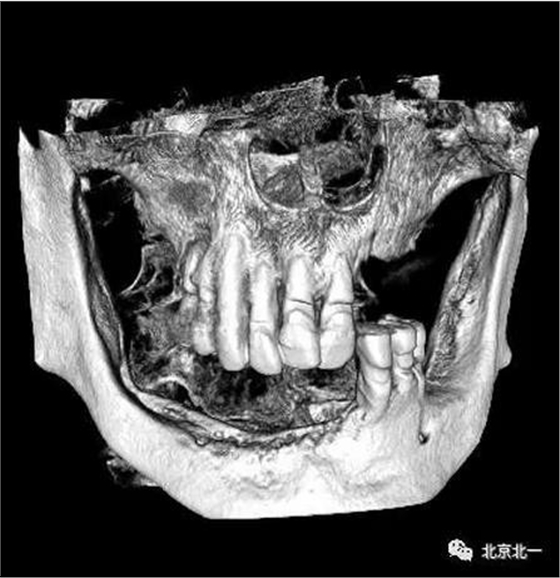

80歲,上頜骨量高度和寬度可, 計劃即刻拔牙+ALL ON 6

下頜已經ALL04

術后CBCT檢查,位置方向理想位置。